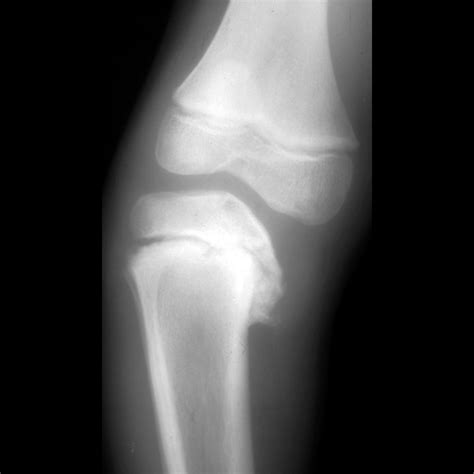

• X-rays: Often the first line of defense for bone fractures or lung issues.

X-ray Minimal Bone fractures, pneumonia, chest congestion